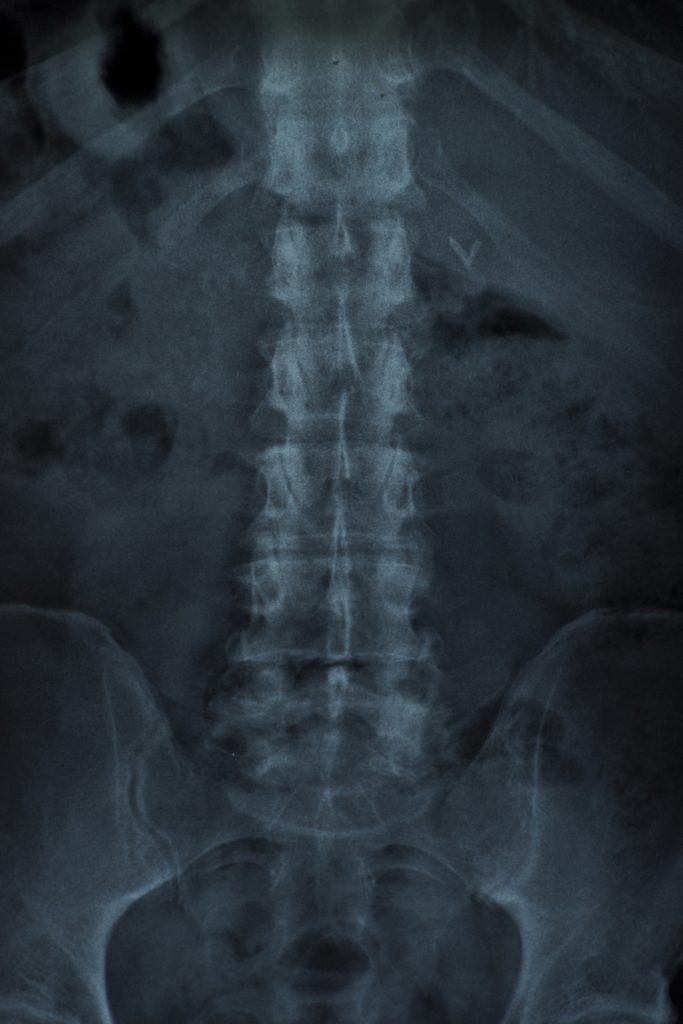

Iliopsoas Tendinopathy/ Iliopsoas Bursitis – Ultrasound Guided Injections